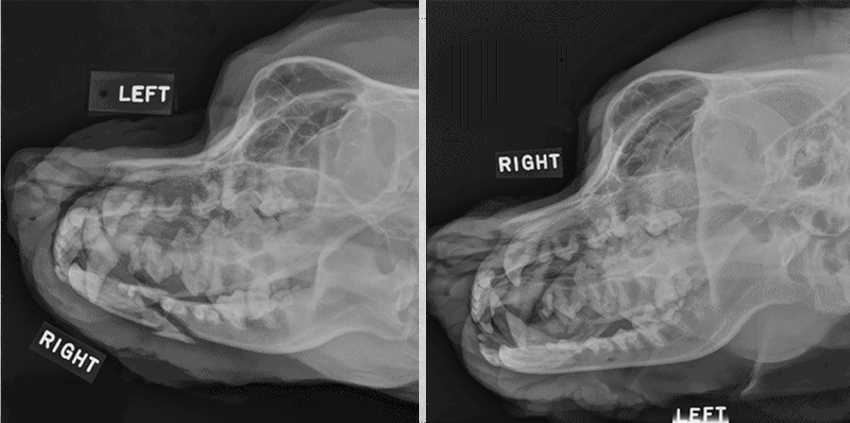

19

Q

identify pathology

A

calvarium neoplasia in left image

mandibular neoplasia in right side image